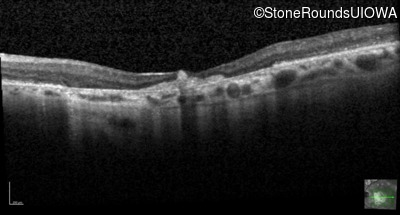

Optical Coherence Tomography - Right - 20/80

Exemplar / OCT Stack

OCT Stack